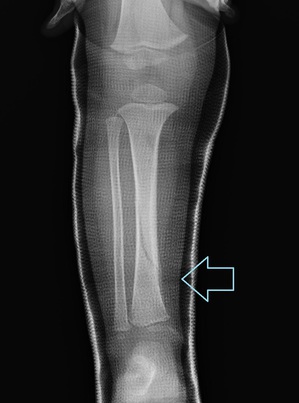

2週間後のレントゲン

15071c.jpg

矢印の部分に仮骨が見えます。

この時点ではギプスのままで2歩くらい歩けるようになりました。